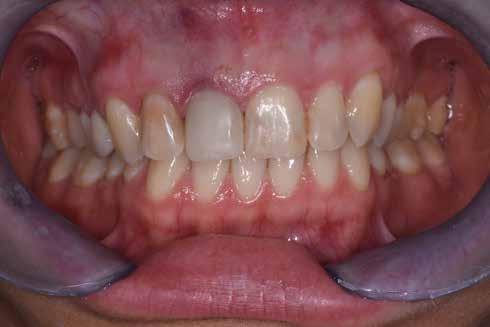

A korai harmicas éveiben járó hölgy rendelőnkbe érkezésének oka a jobb felső nagymetsző fog bizonytalan érzkenysége, elmondása alapján gyermekkorában trauma érte a felső frontrégiót. A frakturált klinikai koronákat kompozittöméssel helyreállították, egyéb kezelést akkor nem tartottak szükségesnek. Az utóbbi hónapokban tapasztalt érzékenység miatt kereste fel rendelőnket. A klinikai vizsgálat (1. és 2. kép) és a CBCT felvétel (3. kép) alapján diagnosztizált külső gyökérreszorpció megoldására a fog eltávolítását, implantátum

A 2020 januárjában elkezdett kezeléssorozat befejezését az év márciusában, hazánkba is begyűrűző Covid-19 pandémia késleltette, így kb. 6 hónap gyógyulás után láttunk hozzá az emergencia profil és a gingivális zenit ideiglenes koronával történő formázásához (11. és 12. kép). A 3 hetente végzett apró alakításokkal sikerült megfelelő ínyprofilt kialakítani, a „rózsaszín esztétika” a páciens számára is megfelelő volt. A bal felső nagymetsző fog meziális kompozit tömés cseréjét követően, individualizált nyitott kanalas lenyomati fejet készítettünk: az akrilát ideiglenes korona profilját átlátszó szilikonnal lemásoltuk, majd a körszimmetrikus gyári lenyomati fej és az ideiglenes korona kontúrja közötti hézagot folyékony kompozittal töltöttük ki (13. kép). Az így készített egyéni lenyomati fejjel vettünk lenyomatot a végleges, kerámialeplezésű cirkónium-dioxid vázas, átmenő csavaros rögzítésű koronához. (A fogtechnikai munkát Nébl Péter fogtechnikusmester készítette.), (14., 15., 16 és 17. képek).

A kész korona átadásakor a páciens elégedett volt az esztétikával, az azóta eltelt évben rendszeres kontrollokon jelent meg, melyek során meggyőződtünk a kemény- és lágyszövetek stabilitásáról (18. és 19. képek).